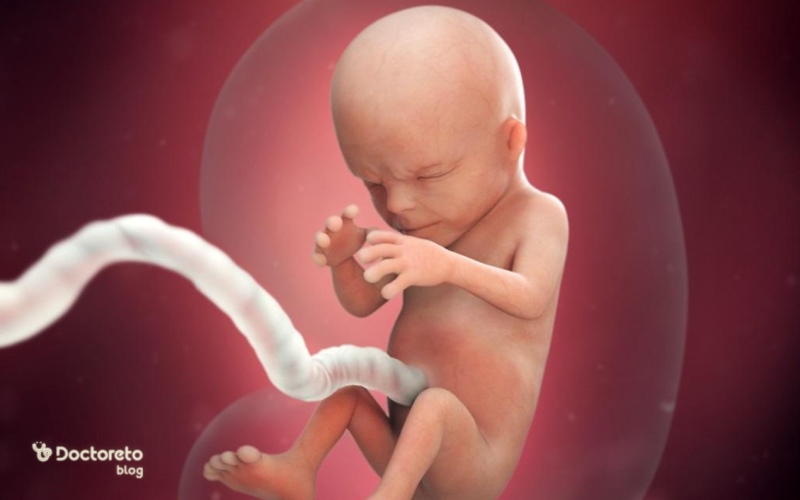

در هفته چهاردهم، جنین حدود ۸.۵ تا ۱۰ سانتیمتر قد و ۴۰ تا ۶۰ گرم وزن دارد. گردن جنین مشخصتر شده، سلولهای قرمز خون تشکیل میشود و اندامهای جنسی رشد کردهاند. جنین حرکات صورت مانند مکیدن انجام میدهد اما مادر هنوز احساس نمیکند. کلیهها ادرار تولید میکنند و موهای نازک ظاهر میشود. سونوگرافی میتواند ضربان قلب را نشان دهد. جنین در مایع آمنیوتیک شناور است و رشد سریع دارد.

در این هفته تغییرات زیر ایجاد میشوند:

- جنین حالات مختلف چهره را تمرین میکند. اگر میتوانستید داخل رحم را ببینید، احتمالا در این هفته مشاهده میکردید که جنین میتواند اخم کند، چشمهای خود را جمع کند و روی صورت خود چروک بیندازد.

- حرکات جنین در این هفته بیشتر میشود. میتواند بازوها و زانوهای خود را خم و صاف کند. برای تمرین تنفس مایع آمنیوتیک را وارد ریهها و خارج میکند. حرکات تند و ناگهانی سهماهه قبل از بین رفته و حرکات صاف و روان شده است.

- اندامهای جنسی خارجی رشد میکنند.

- اولین حرکات روده (مکونیوم) شروع میشود.

- کبد میتواند صفرا تولید کند.

- تولید هورمون در غده تیروئید شروع میشود.

- کمی مو جوانه میزند و ابروها پر میشود. موهای کرکی سطح بدن، جنین را گرم نگه میدارند. با ساخت چربی در بدن جنین، این موهای کرکی میریزد.

در هفته چهاردهم بارداری جنین چه شکلی است؟

جنین در این هفته بهسرعت در حال رشد و تکامل است و تقریبا اندازه یک پرتقال میشود. دست خود را مشت کنید؛ جنین تقریبا به این اندازه رسیده است. گردن جنین در هفته ۱۴ بارداری بلندتر میشود و چهره بیشتر قابل تشخیص است. شاید برایتان جالب باشد که بدانید در حال حاضر تمامی بدن جنین را موهای کرک مانند شبیه به پرزهای هلو فرا گرفته است.

حرکات جنین در هفته چهاردهم

حرکات جنین در هفته چهاردهم شروع شده اما مادر معمولا تا هفته ۱۶ تا ۲۰ احساس نمیکند. جنین مشت میزند و عضلات صورت را تمرین میدهد. این حرکات برای رشد عضلانی ضروری است. سونوگرافی میتواند حرکات را نشان دهد.

در هفته چهاردهم بارداری جنین میتواند حرکات جدیدی انجام دهد. دست و پاهای خود را خم و صاف میکند. میتواند اخم کند و چشمان خود را جمع کند. در این هفته جنین حدود ۹ سانتیمتر میشود. اگر دست خود را مشت کنید، اندازه تقریبی جنین را متوجه میشوید. کبد صفرا تولید میکند و تولید هورمون از غده تیروئید شروع میشود. موهای کرک مانند، سطح بدن جنین را میپوشاند.